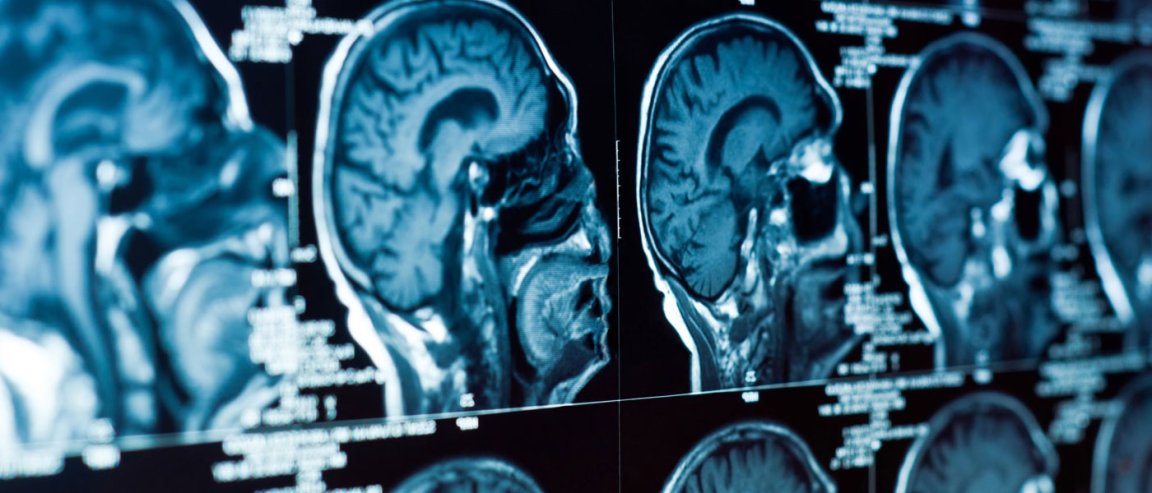

According to their research published in the neurology journal Brain, depression results from connection pattern changes in a key area of the brain called the orbifrontal cortex (OFC). The researchers used a high-precision MRI to scan the brains of more than 900 people, of which 421 were patients with major depressive disorder. They found that feelings of loss and low self-esteem are directly linked to two sides the OFC — the medial OFC and the lateral OFC.